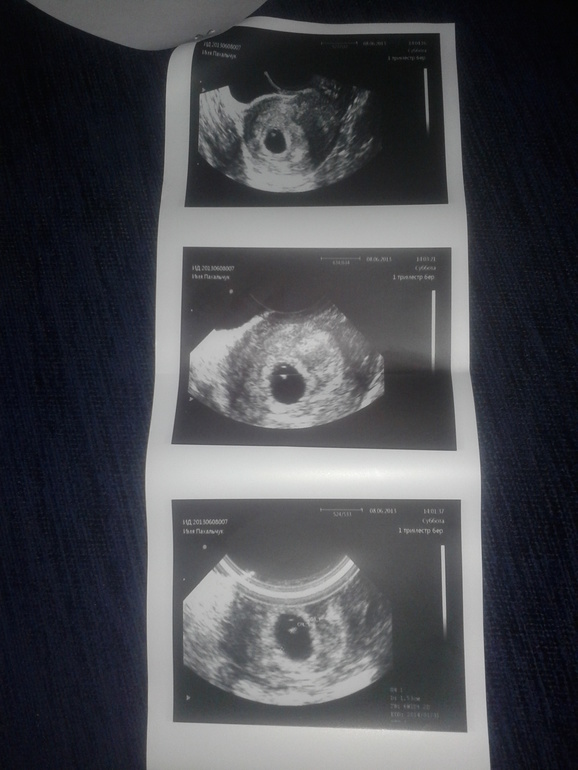

Первое узи и наша бусинка: